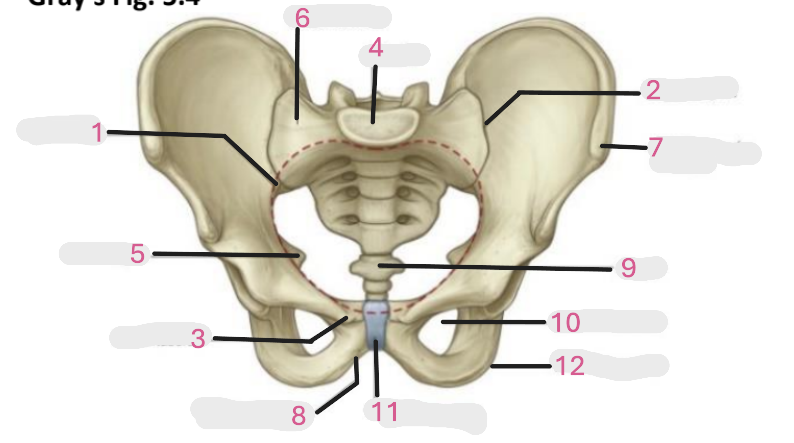

Where is the iliac crest

1

where is the sacral canal

2

Where is the iliac tubercle

3

Where is the outer lip

4

Where is the inner lip

5

Where is the iliac fossa

6

Where is the pectineal line (pecten pubis)

7

Where is the sacroiliac joint

8

Where is the ischial spine

9

Where is the iliac tuberosity

10

Where is the promontory

11

Where is the arcuate line

12

Where is the anterior superior and inferior iliac spine

13

Where is the intermediate line

14

Where is the ala of the sacrum

15

Where is the coccyx

16

Where is the pubic crest

17

Where is the pubic tubercle

18